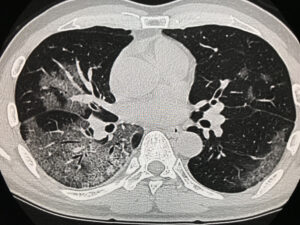

典型的な「COVID-19」のCTスキャン像…これは肺炎にかかった部分が、丁度「メロンの表皮」パターンの様になっているところから「Crazy paving pattern」と呼ばれているようです。